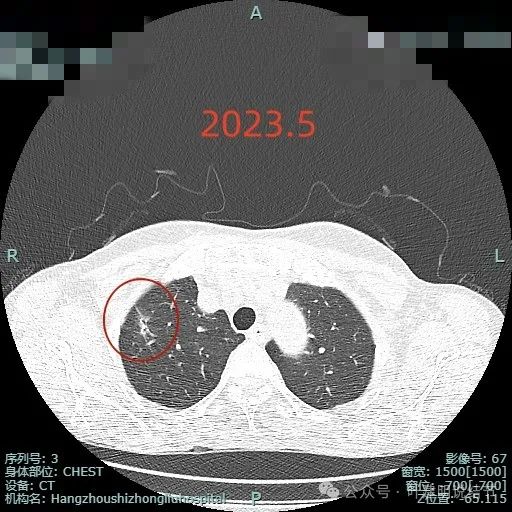

2023年时病灶内有扩张的细支气管出现,说明病灶内的肿瘤成分有一定的收缩力,影响灶内的细支气管。瘤肺边界稍显糊,毛刺稍显长,胸膜牵拉不太明显,病灶整体有点偏长条状。

2024年5月时病灶范围较前扩大,灶内实性成分占比增多,毛刺明显,表面不平,分叶可见。